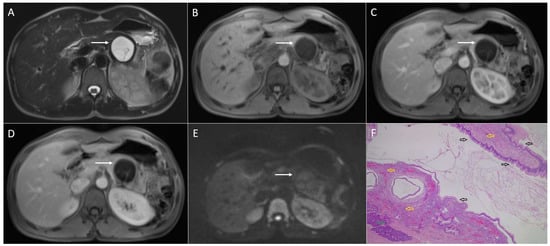

4. Solid Pseudopapillary Neoplasm Mimicking Cystic Pancreatic Lesions

4.1. Serous Cystadenoma